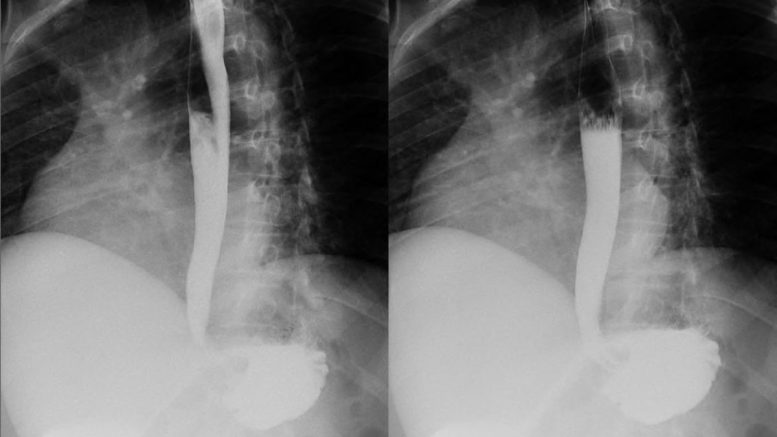

Avant de plonger dans la profondeur de son importance, il est essentiel de définir ce qu’englobe le TOGD. Essentiellement, il s’agit d’une radiographie spécifique de l’œsophage, de l’estomac et du duodénum. Cette procédure demande au patient de consommer un produit de contraste, généralement à base de baryum, qui rendra visible ces organes sur les clichés radiographiques. Les images obtenues permettent alors aux médecins d’identifier diverses anomalies telles que les ulcères, les tumeurs, et les rétrécissements des conduits digestifs.

Le TOGD occupe une place centrale dans le diagnostic des pathologies gastro-intestinales pour plusieurs raisons. Premièrement, cet examen offre une visualisation directe et détaillée des structures anatomiques internes, ce qui aide considérablement à repérer d’éventuelles anomalies structurelles ou fonctionnelles. De plus, sa capacité à différencier les conditions pathologiques des problèmes fonctionnels est inégalée, car il montre non seulement la forme mais aussi le mouvement des liquides à travers le système digestif.